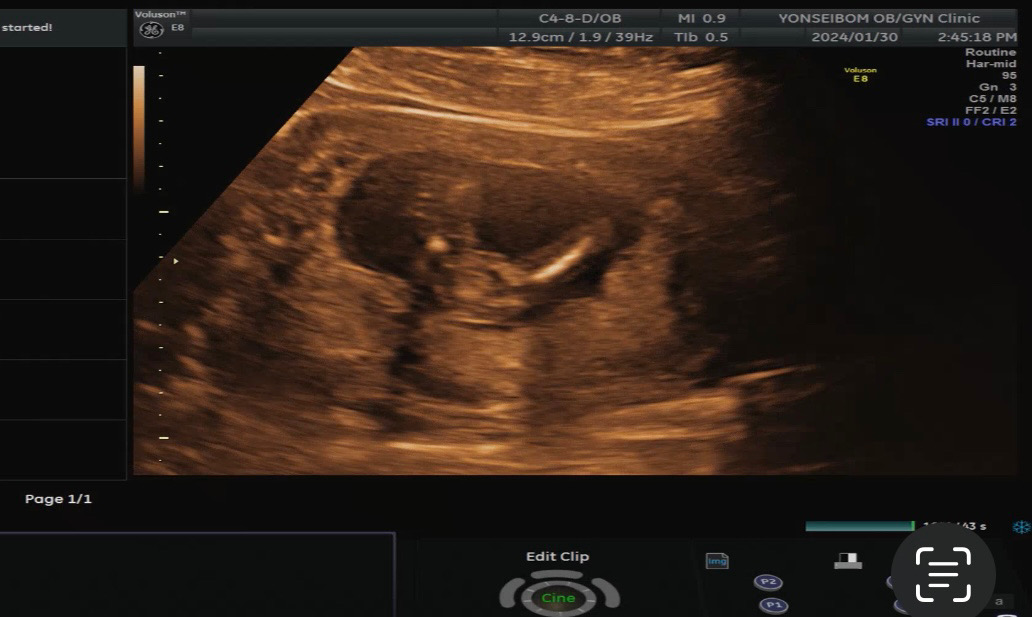

이정도면 성별 나왔다고 봐도 되겠죠?

14주 6일인데 다리사이가 아주 매끈해요..! 이정도면 딸이라고 봐도 되겠죠? 🫢🫢 의사선생님께 슬쩍 물어보니 지금은 확실하지않은데~ 아직 모르는데~ 라고 하시면서도 사이가 매끈하다고 힌트주셨어요 ❤️🥺❤️

있다가 없어지는(?)건 봤는데 없다가 생기기도 하나요?! 🥺🥺

있다가 없어지는건 거의 잘 없는 경우에용 그 주수부터는 없다가 생겼다기보단 숨겨져서 잘 안보였던게 보이는거죵